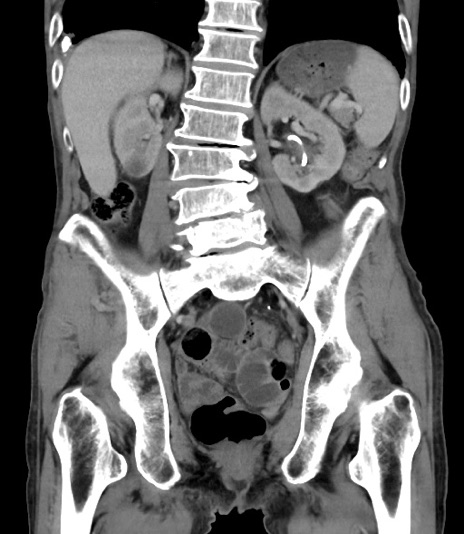

症例3(冠状断像)

【症例】 70歳代男性

【主訴】右鼠径部腫瘤、疼痛

【現病歴】本日朝より上記主訴あり、受診。

【既往歴】膀胱癌にて膀胱全摘、両側尿管皮膚瘻

【データ】WBC 5600、CRP 0.56